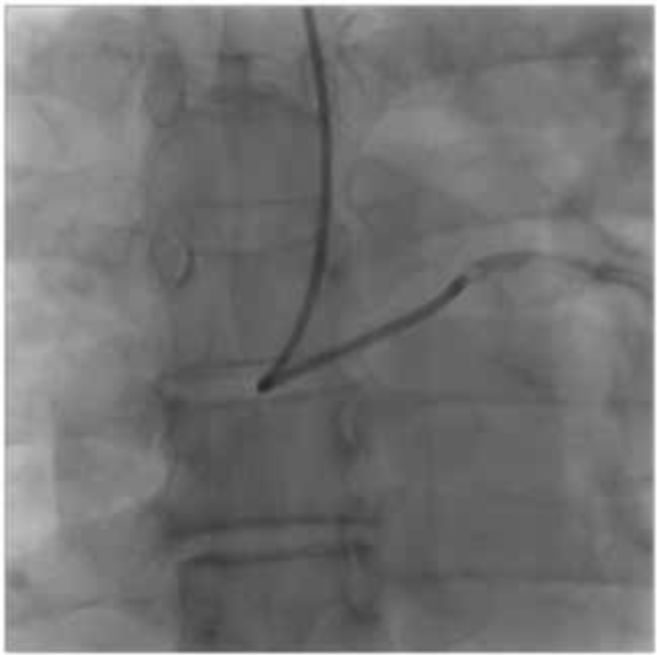

IVUS观察病变后,首先在#6~7的支架内用3.5 mm Lacrosse NSE18atm进行预扩,接着SION blue保护D2,用2.0 mm LAXA对#7进行预扩,在LAD中植入Xience Xpedition 2.25 mm×28 mm覆盖D2。利用Crusade将SION blue再次送入D2、在LAD/D2处用2.25 mm的SDB(支架球囊)/2.0 LAXA进行KBI。接着用SION blue对D1进行保护,与之前植入的Xience重叠,植入Xience Xpedition 3.5 mm×33 mm将BMS完全覆盖。利用Crusade将SION blue送入D1,在LAD/D1尝试用3.5 mm SDB/2.0 mm LAXA进行KBT,因为3.5 mm SDB很难通过,所以将导引导管做成α圈状提高支撑性,同时用2atm反复扩张收缩SDB,将球囊顺利通过。(图3